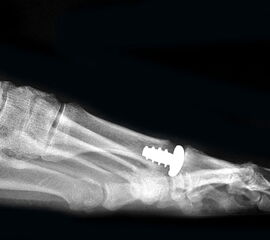

Resultate:

Die ersten Versuche mit der Prothetik am Großzehengrundgelenk wurden mit metallischen Hemi-Implantaten (Abb. 13, 14) vorgenommen. Eine Studie 47 mit größerem Kollektiv im Langzeitverlauf zeigte befriedigende Resultate, trotzdem hat sich die Technik bis heute nicht wirklich durchgesetzt. Der gleiche Autor verglich die Endoprothese mit der periartikulären Osteotomie und konnte keine wesentlichen Unterschiede feststellen 48. Eine neuere Studie vergleicht die Hemiarthroplastik mit der Arthrodese und der Resektionsarthroplastik und kann keine signifikanten Unterschiede feststellen 49. Metall–Polyäthylen-Paarungen zeigten eine hohe Lockerungsrate der Komponenten, weshalb sich diese Paarung ebenfalls nicht durchsetzte 505152. Am meisten Erfahrung besteht mit der Silikonprothese. Initial als Hemiprothese propagiert 46, wurde wegen mangelhaften Erfolgen 5354 die Totalprothese mit zwei Schäften eingeführt 55. Die Langzeitergebnisse sind widersprüchlich 55565758 so dass wegen der Verunsicherung dieses Model aktuell nicht regelmässig zum Einsatz kommt.